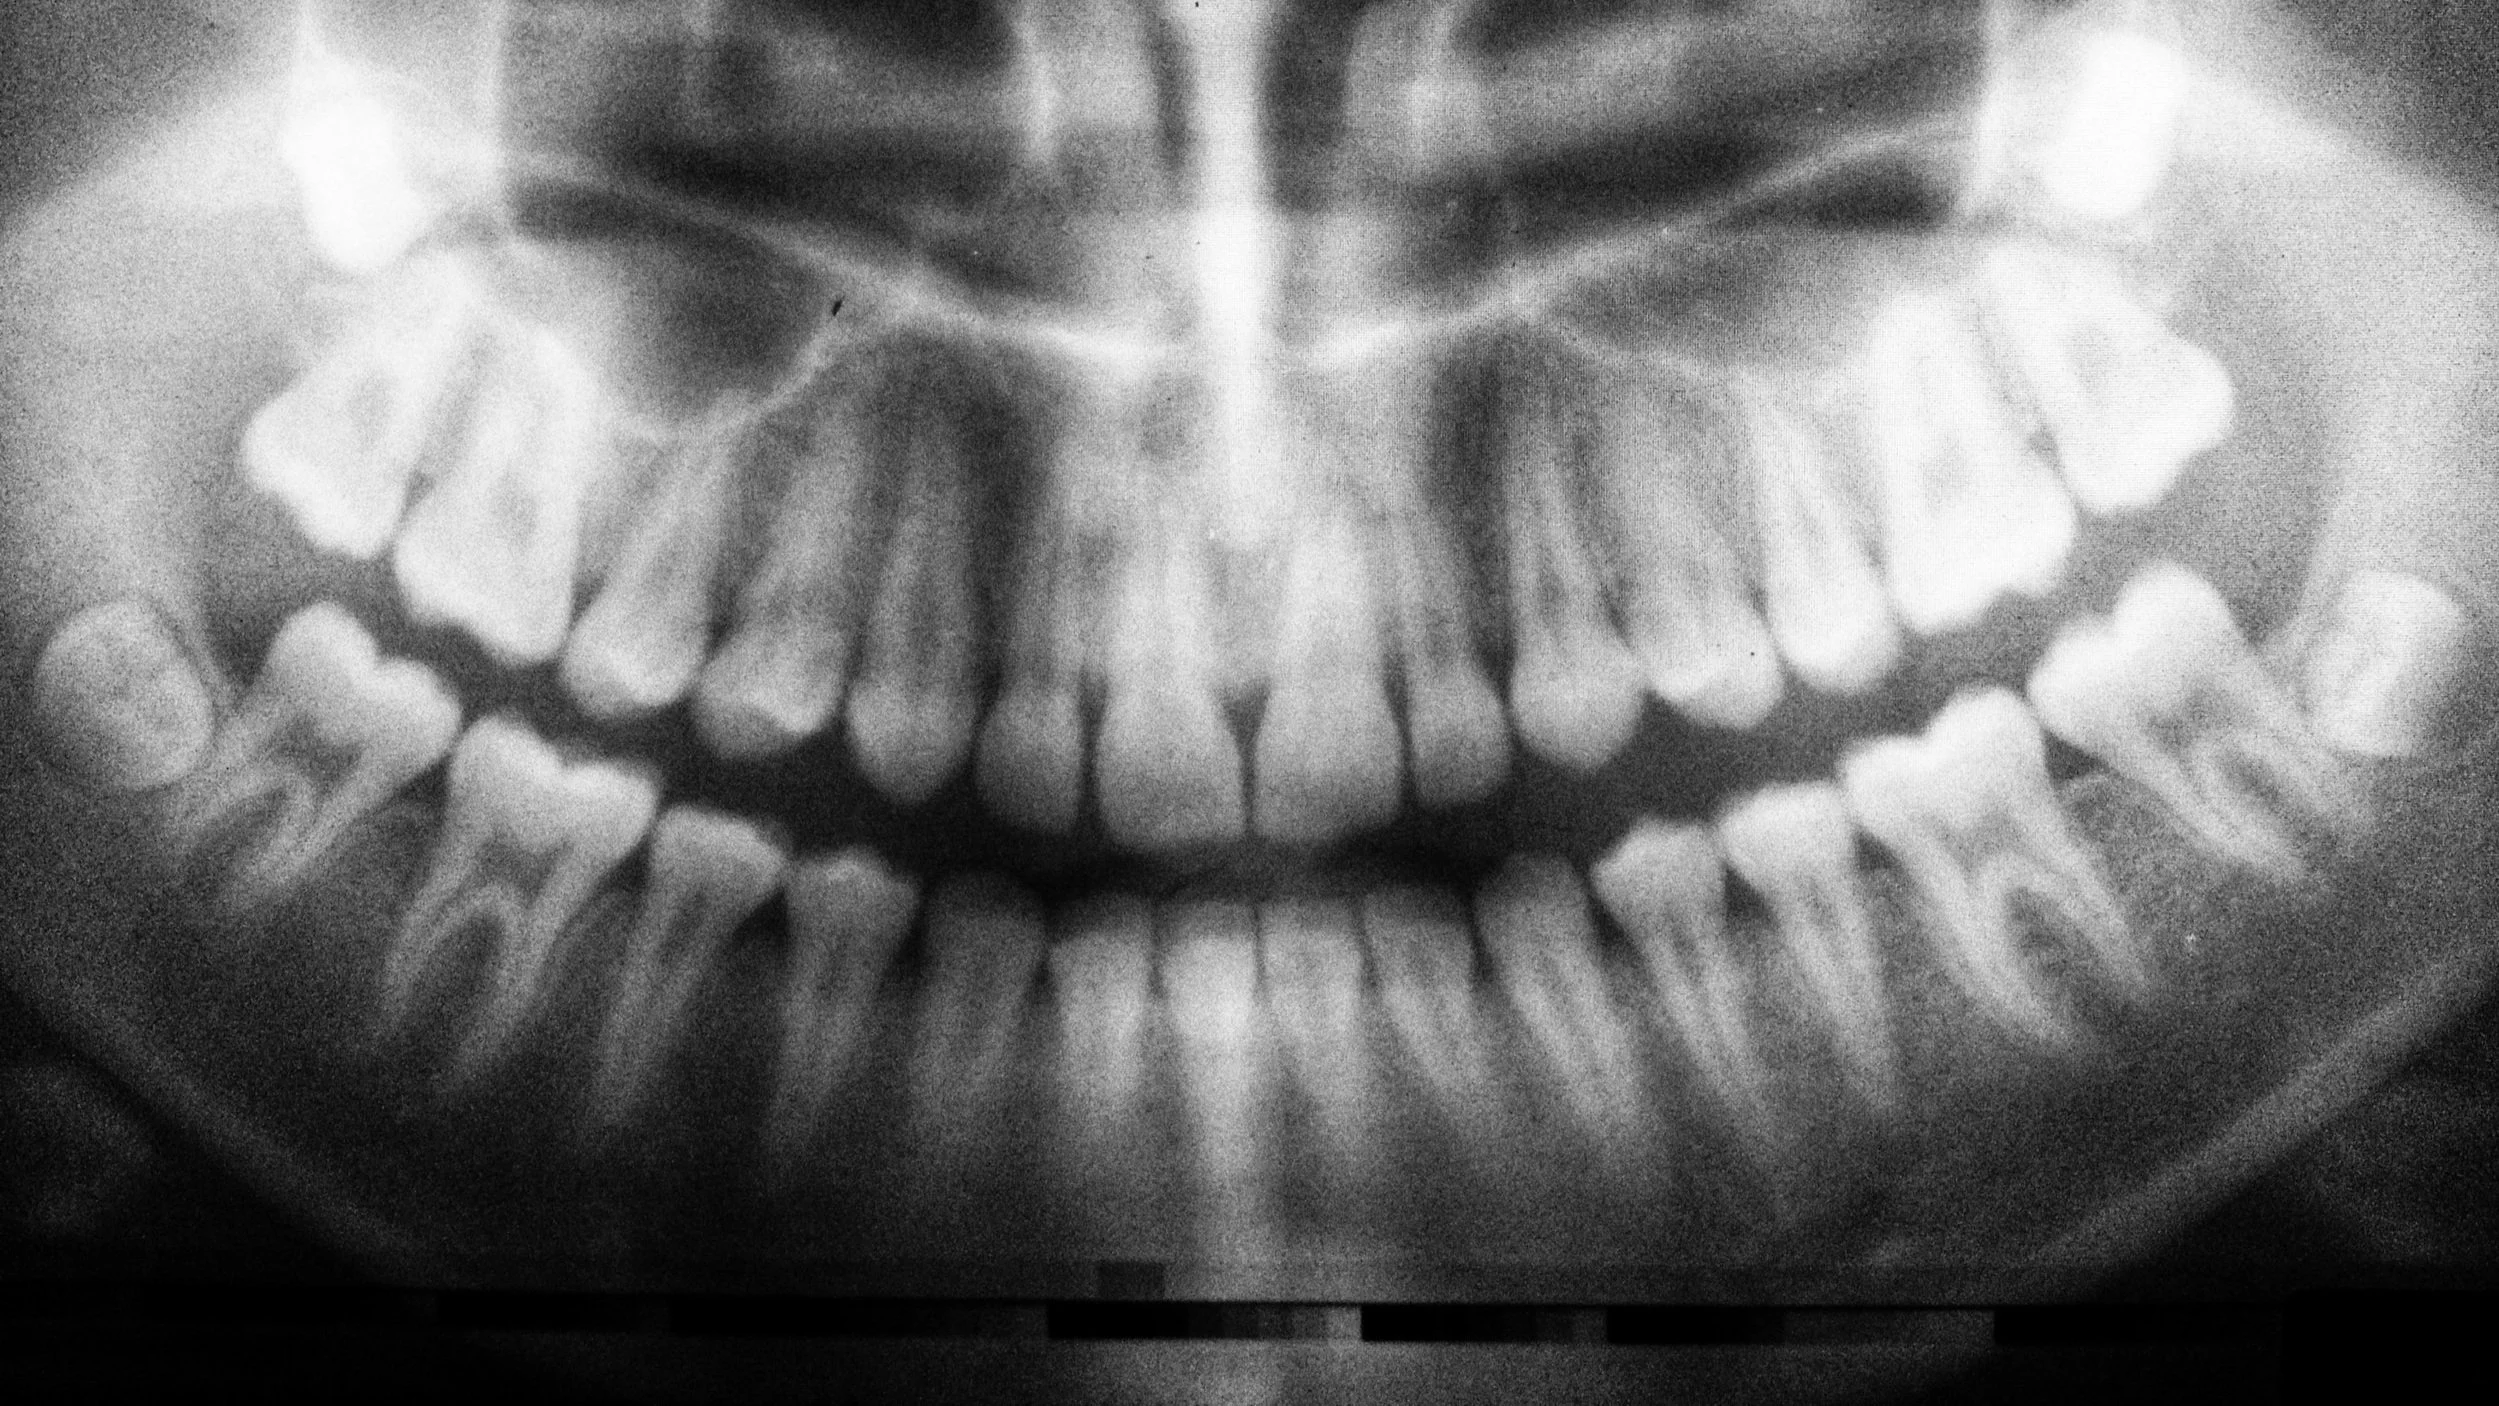

Dental hygienists rely on a variety of tools to perform their duties. These include hand instruments like scalers and curettes, ultrasonic tools that use vibration to remove deposits, and polishing devices to clean and shine teeth. Digital X-ray machines and intraoral cameras help hygienists document conditions and assist dentists in diagnosing problems.

Taking and developing dental radiographs (X-rays) is another key task. These images help both the hygienist and dentist identify issues that might not be visible during a standard exam, such as bone loss or cavities between teeth.